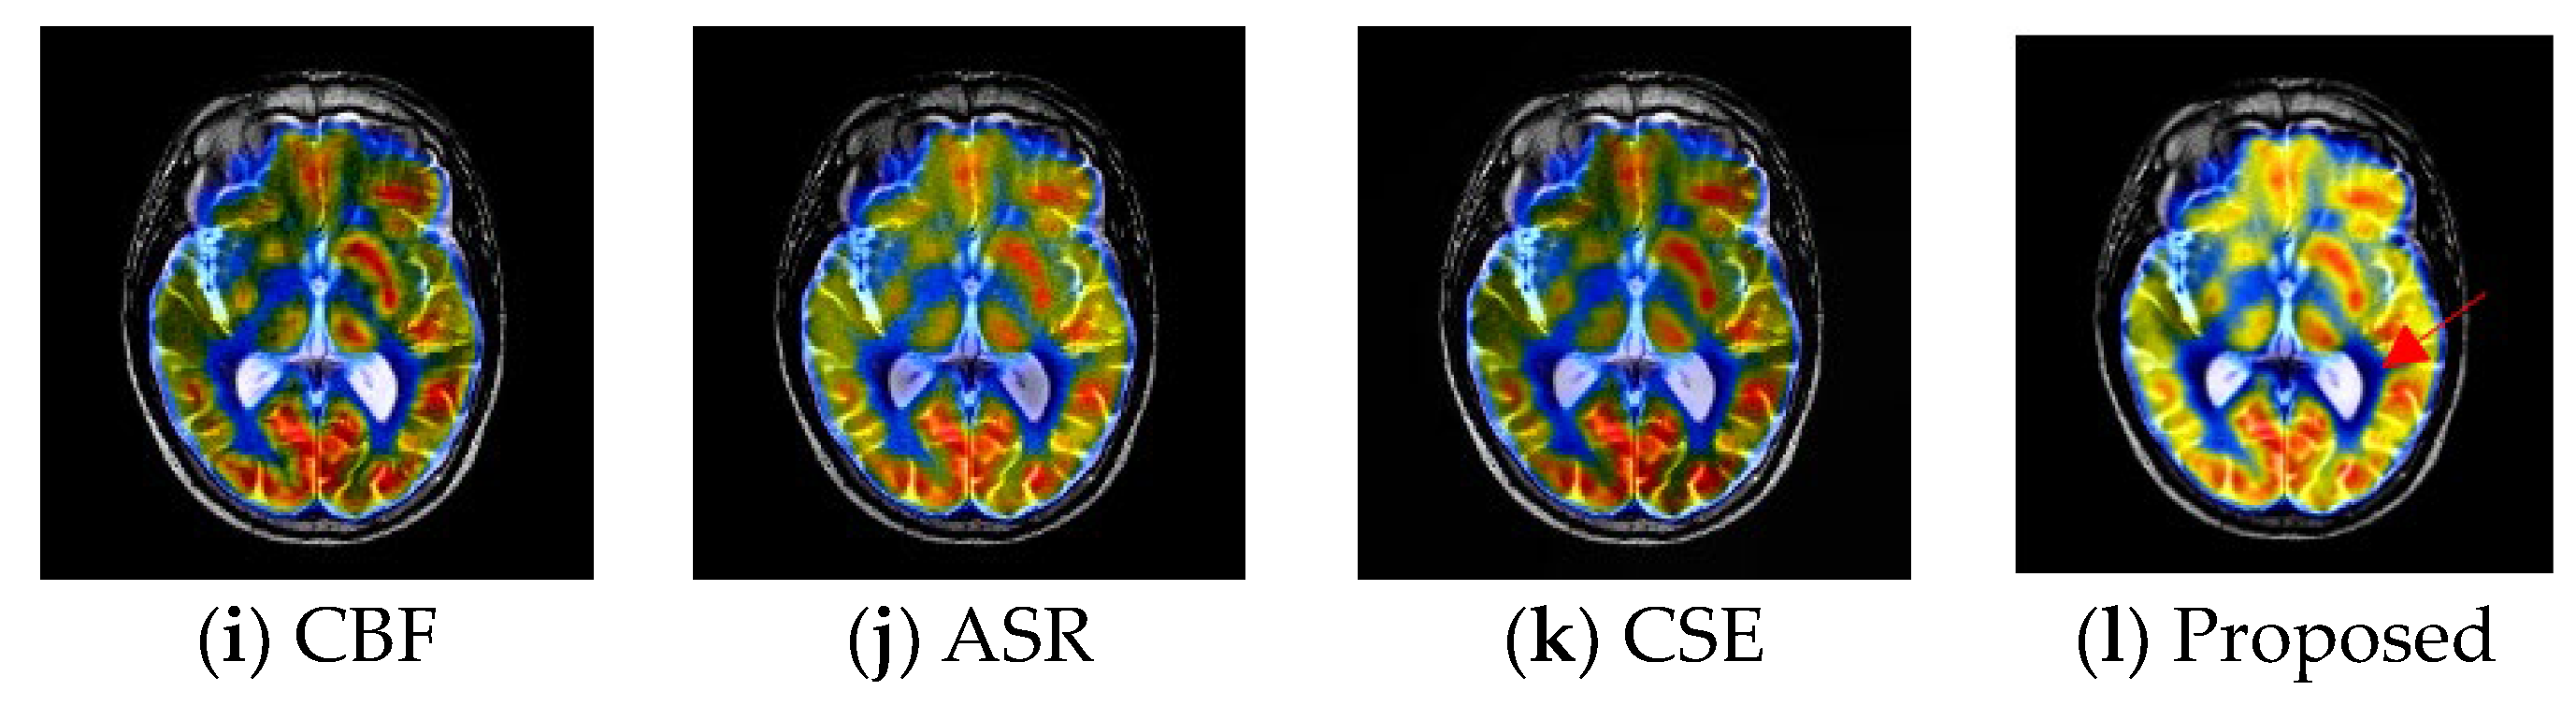

4.4. Experimental Results